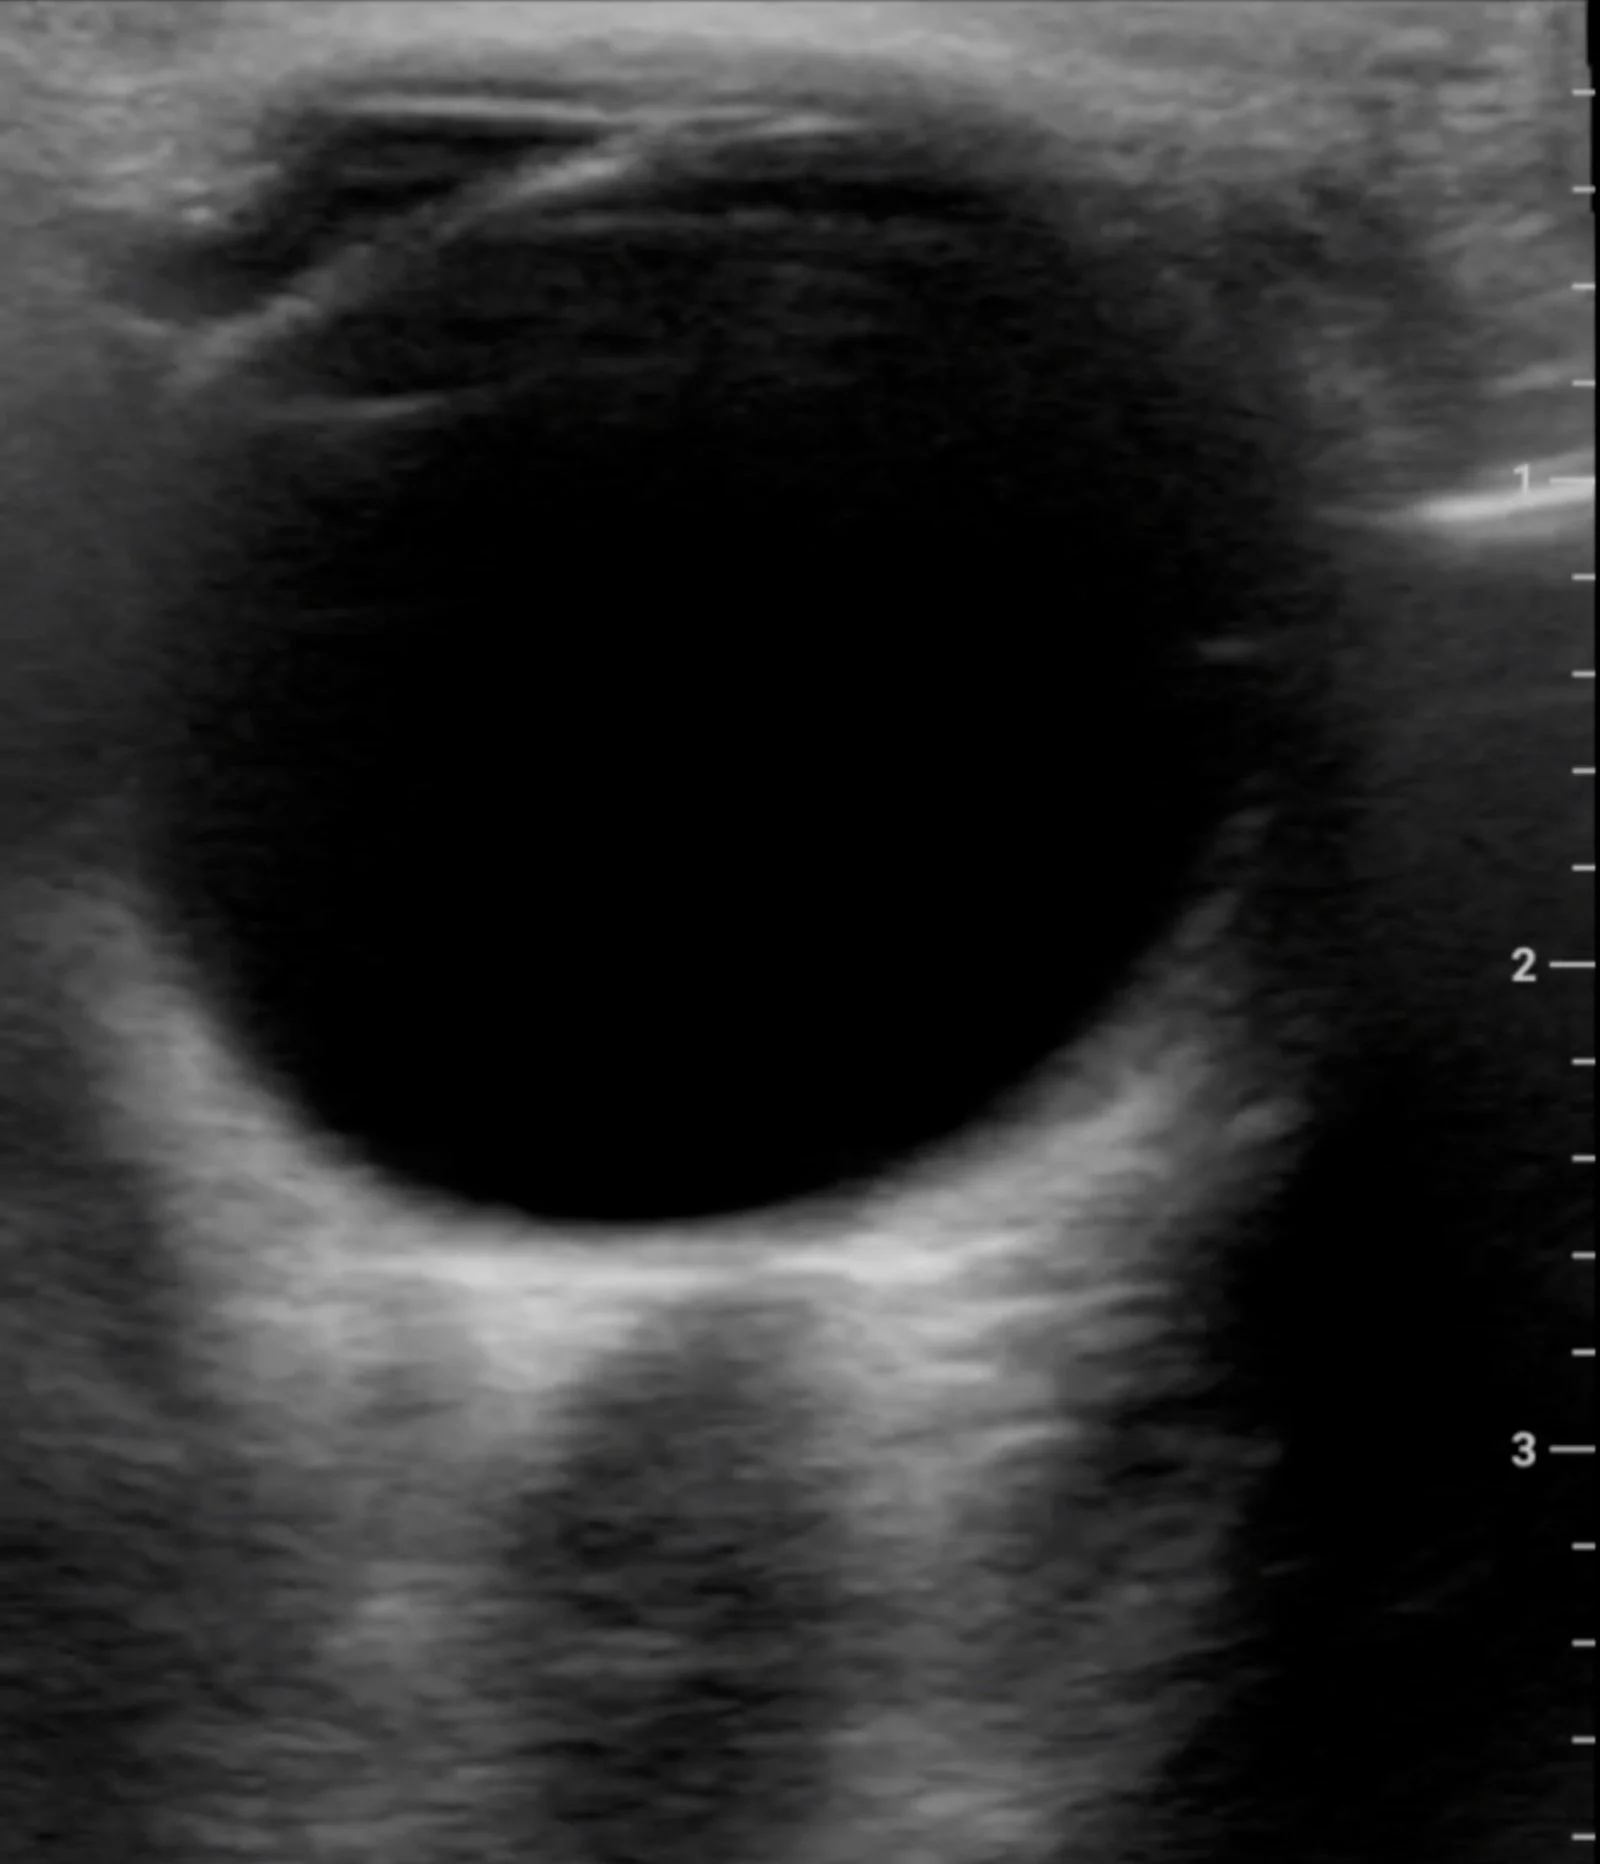

Ultrasound Images

This model of my eye was created using images captured by the device.